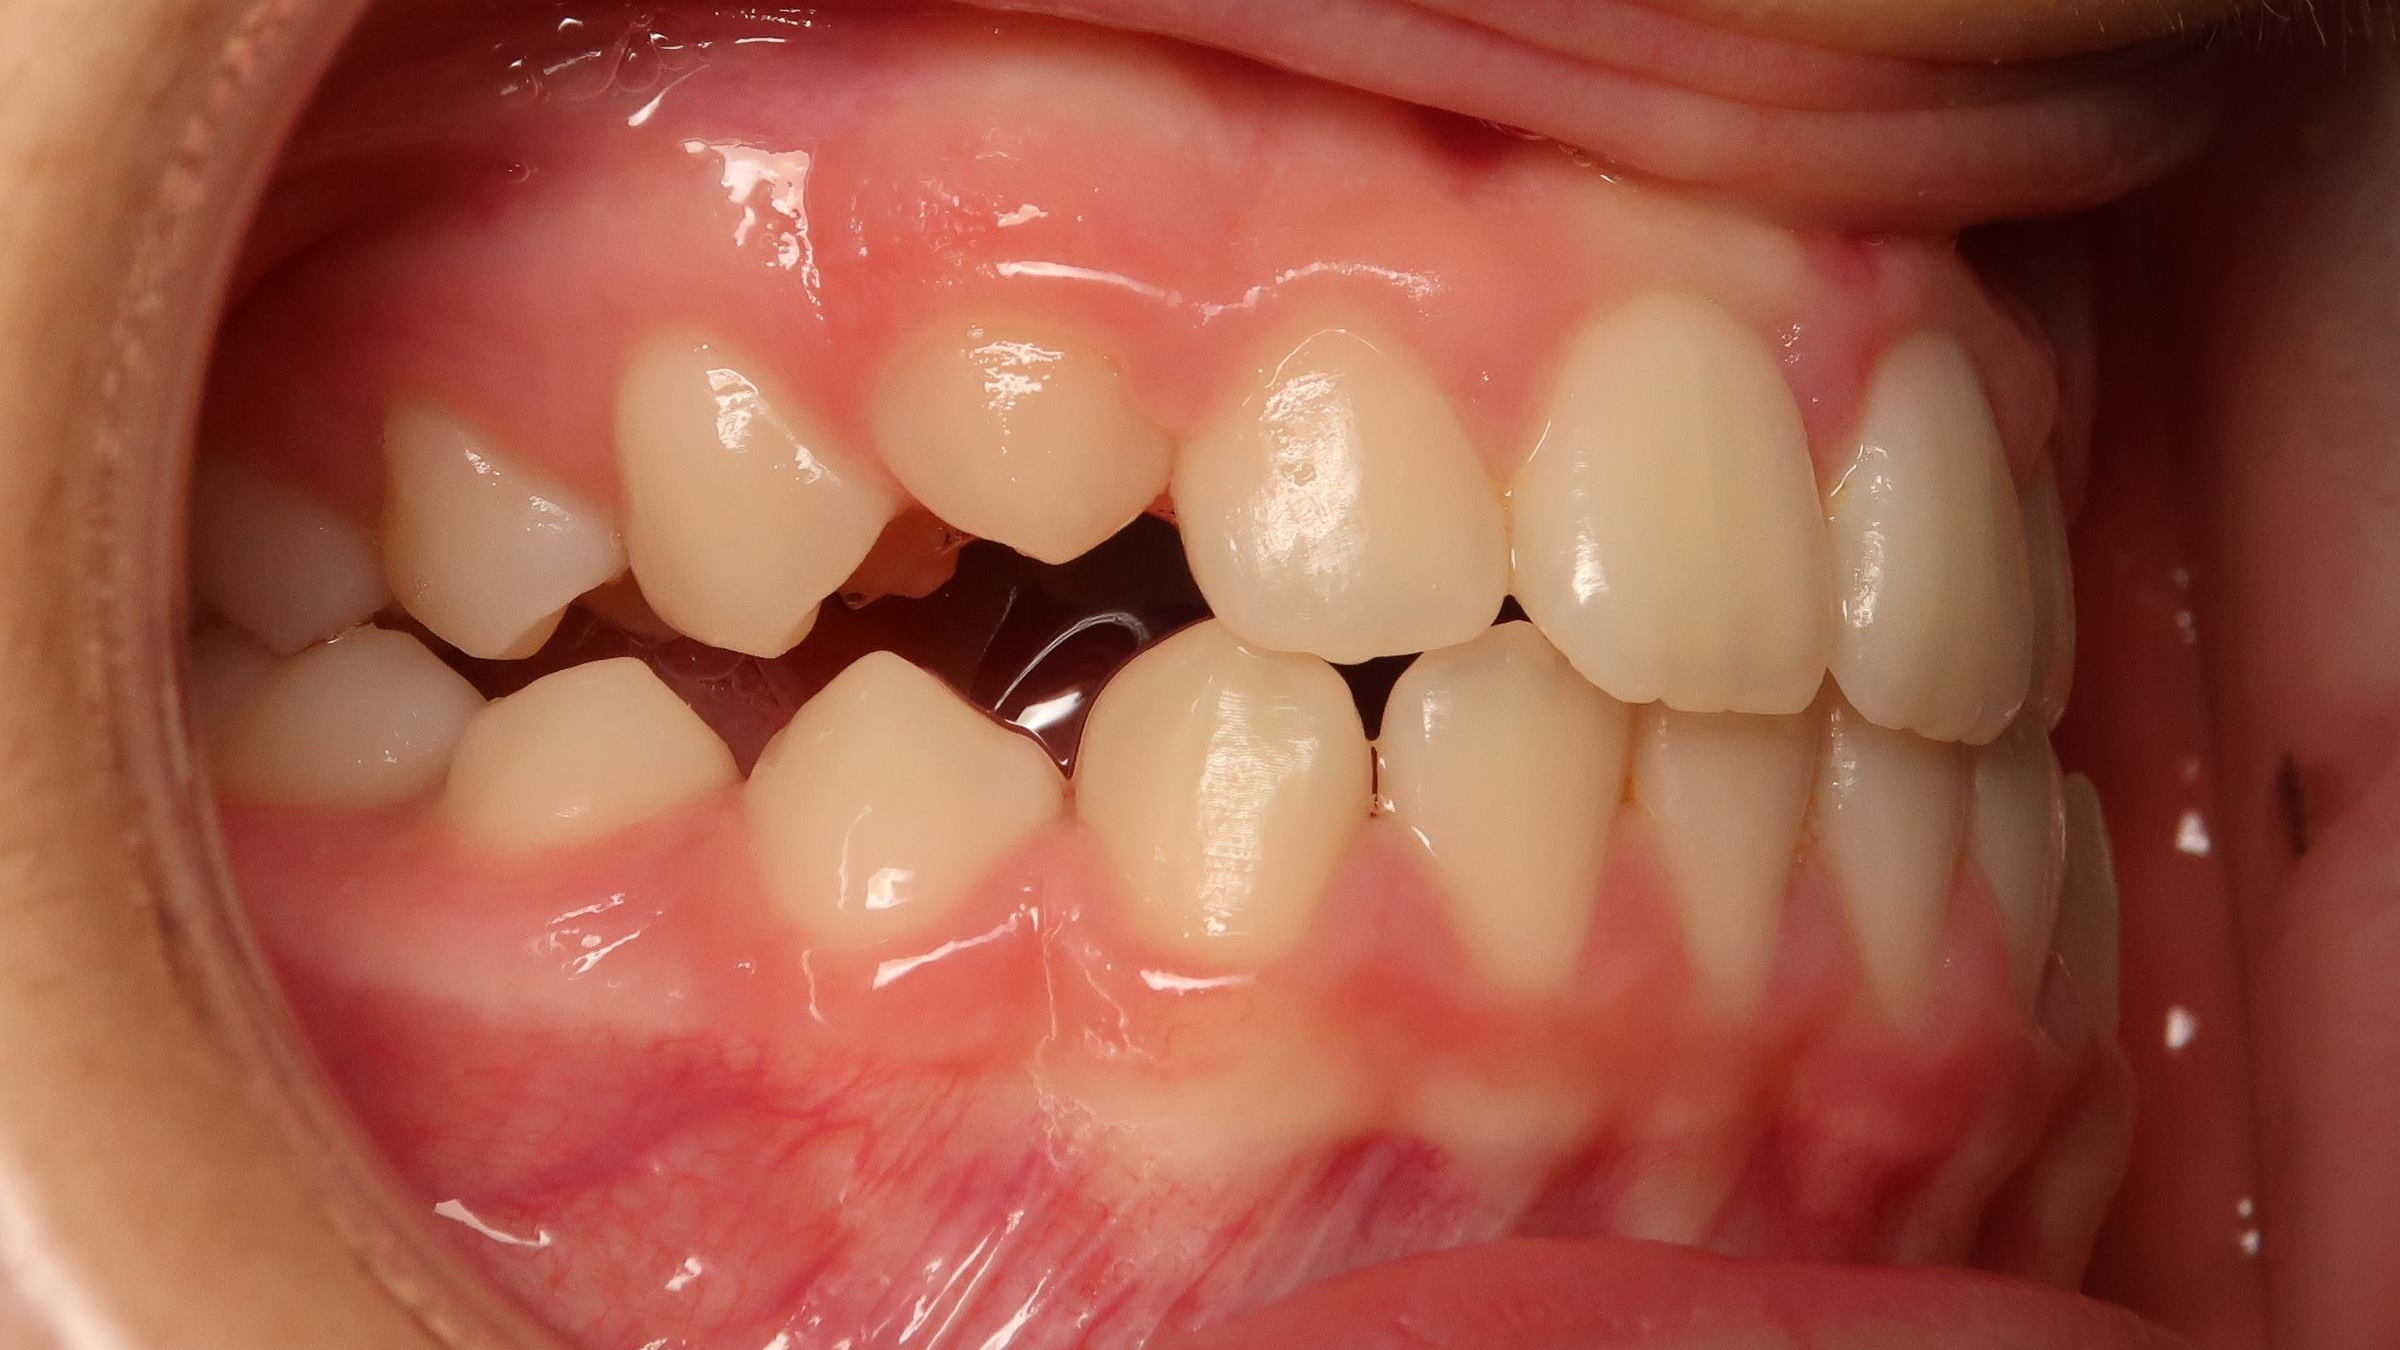

25. bout à bout anterieur 6 ans

dents du haut bout à bout par rapport à celle du bas